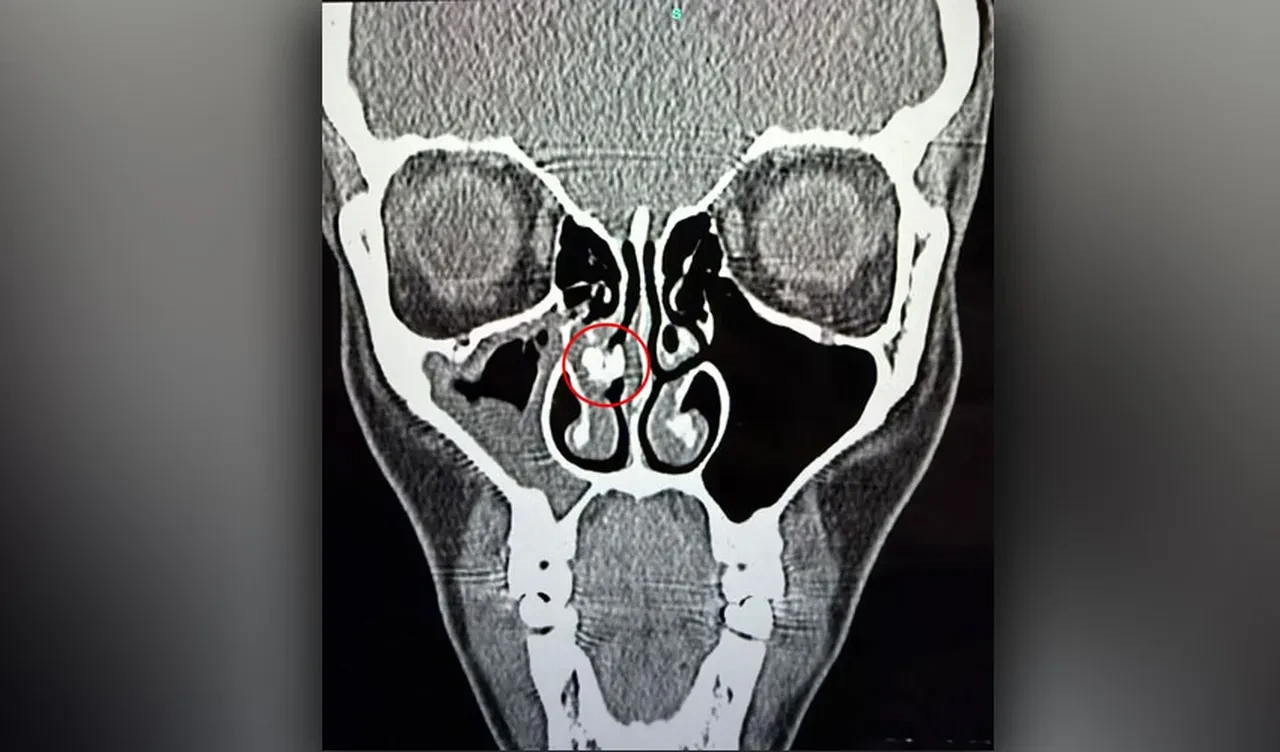

Geçtiğimiz yıl ağır bir sinüzit geçirmesiyle tomografi çekildi ve burnunda kireçlenmiş bir yabancı cisim olduğu ortaya çıktı. The Sun'ın haberine göre, doktor endoskopla baktığında tıkanıklığı net şekilde gördü ve bir saatlik uğraşın ardından çıkarmayı başardı. Candela'nın burnundan çıkan herkesi şaşırttı; katlanmış ve yuvarlanmış bir parça yapışkan banttı.